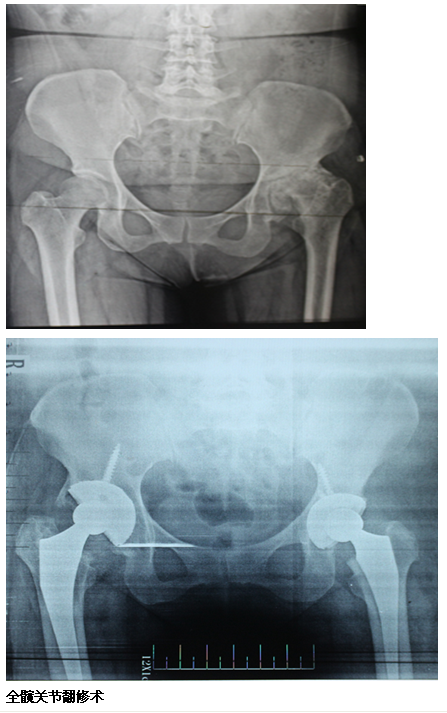

关节骨科组:我院是全市最早开展关节置换的医院之一(1987年开展全髋关节置换手术,2003年开展肩关节置换手术,2007年开展全膝关节置换手术)以治疗各类关节疾病为特色,成功开展人工关节置换术,包括对股骨颈骨折,膝关节骨折和退变等进行人工(全)髋关节,膝关节及肩关节置换等手术,已达国内先进水平;对高龄患者股骨粗隆间粉碎性骨折的人工关节置换,股骨头无菌性坏死晚期人工关节置换,全髋关节翻修术等诸多疑难复杂的人工关节置换,翻修术积累了丰富经验。